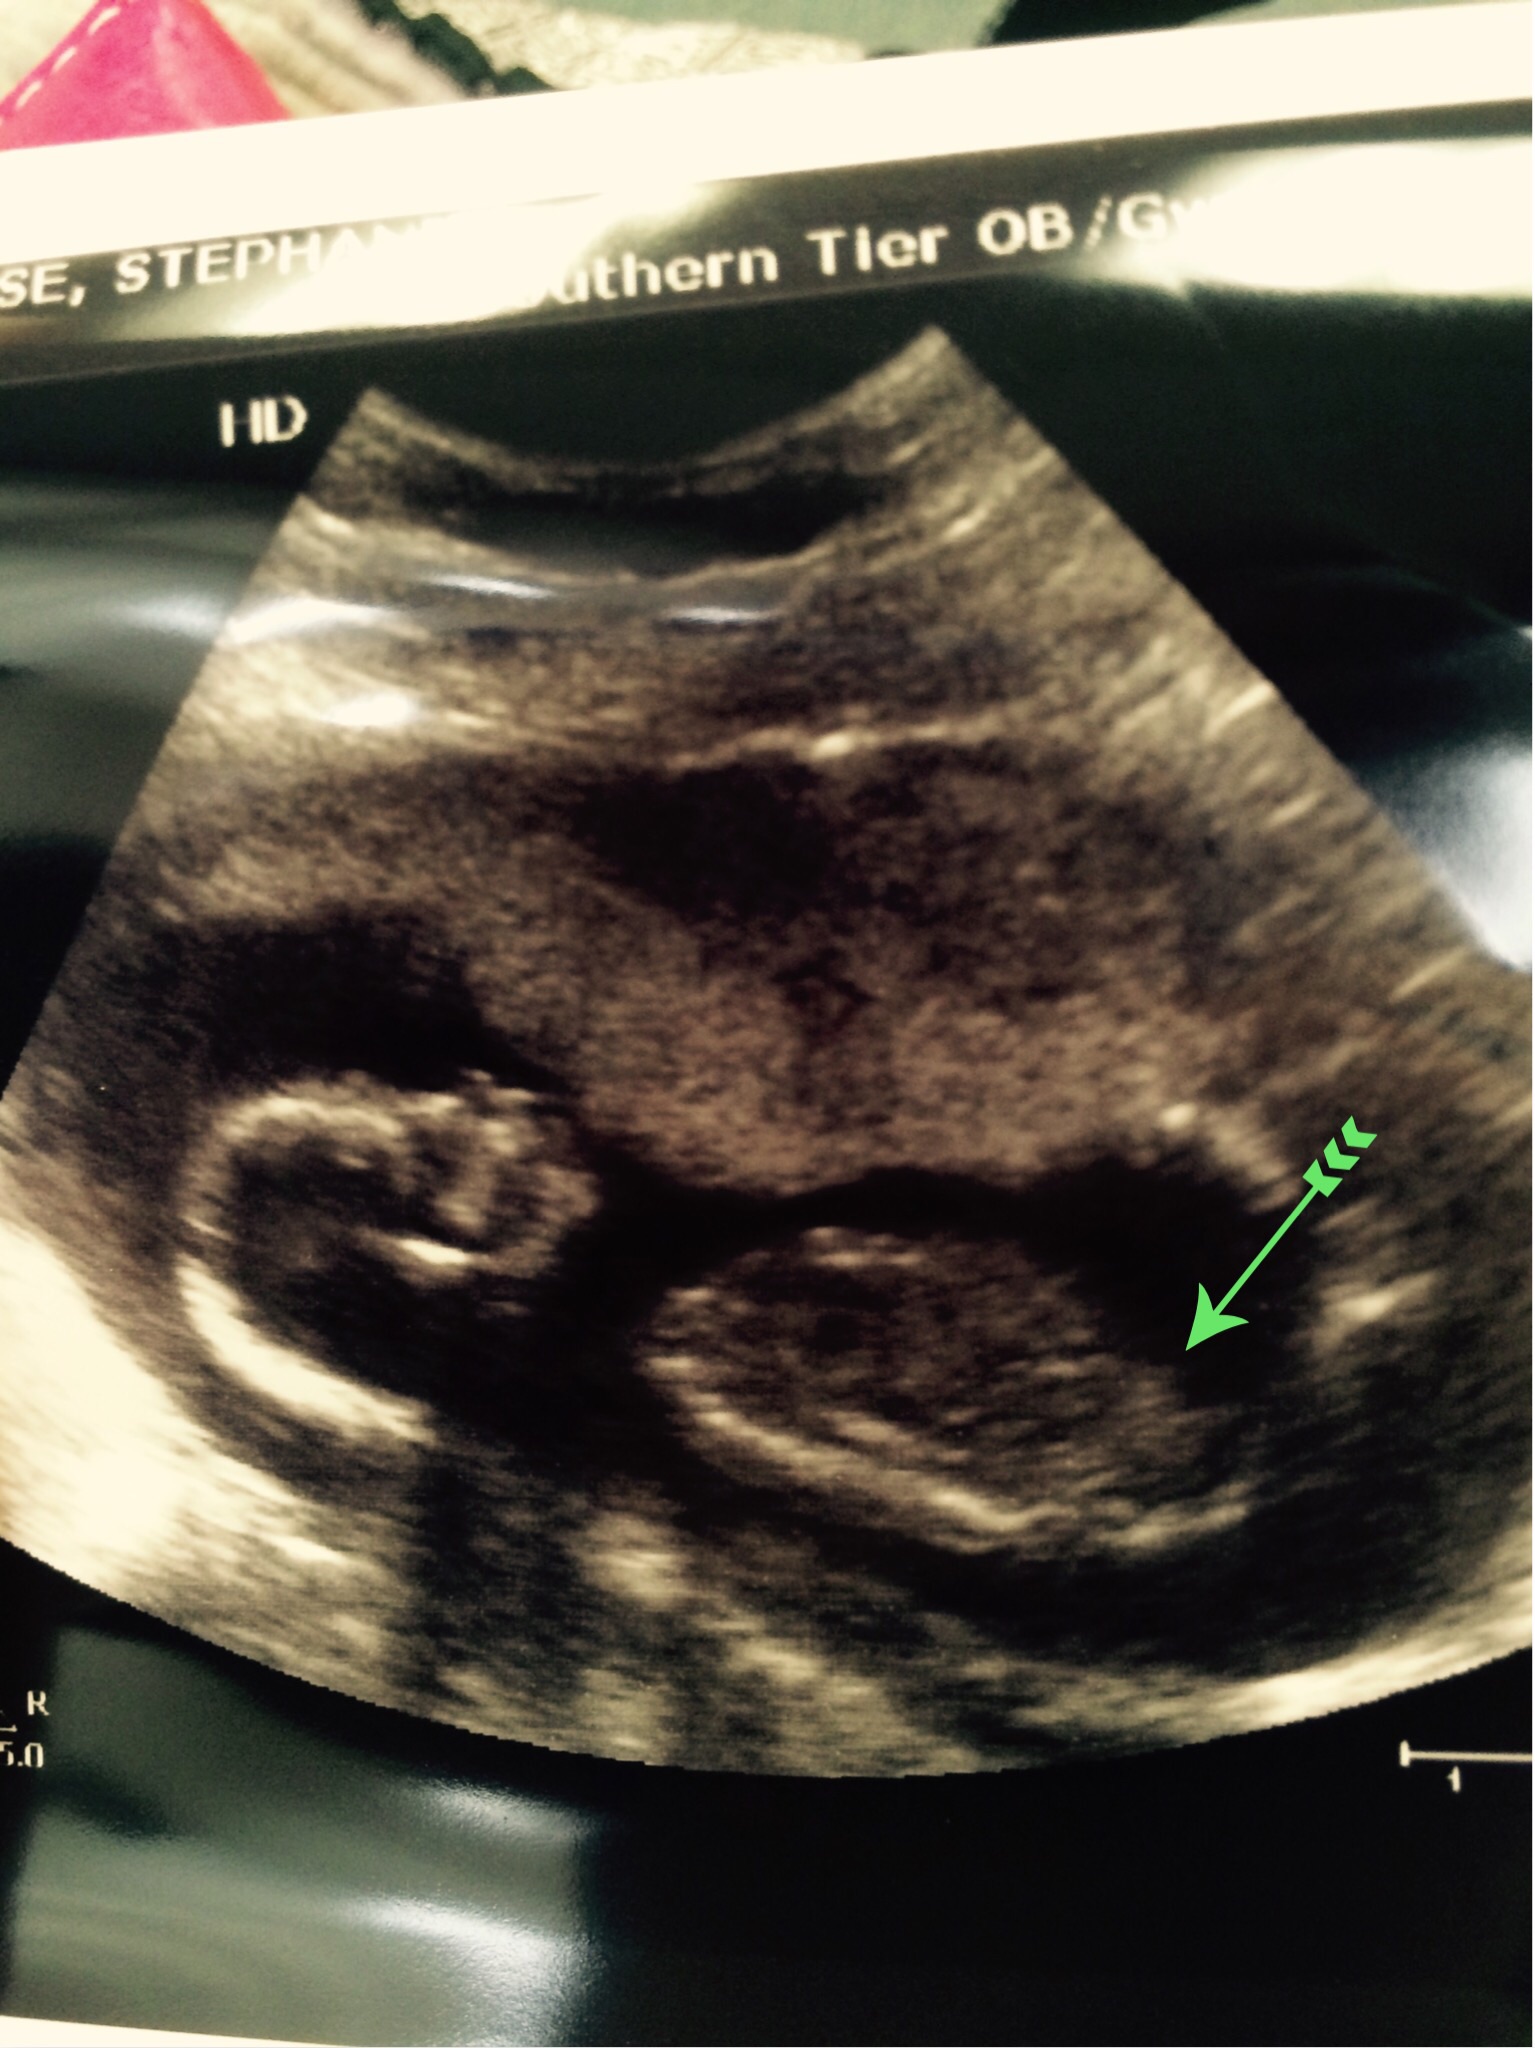

1 Attachment(s)

This the only potty shot I got. Not sure if is very reliable. Attachment 24388